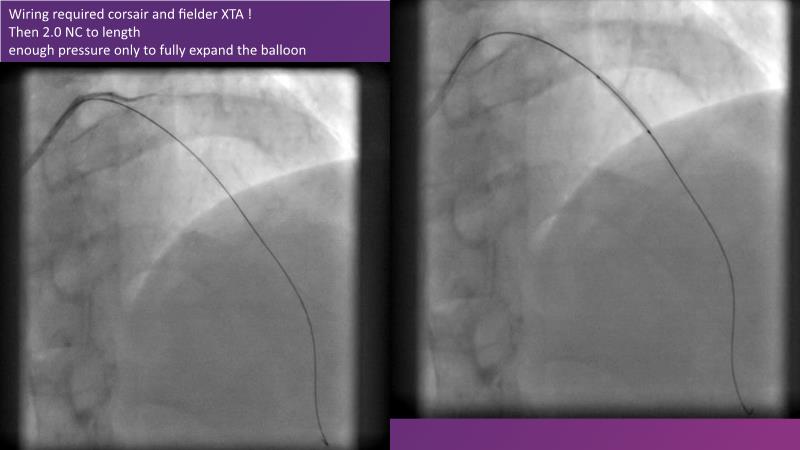

DES and DCB, can these two technologies be complementary for the treatment of the same patient? What are the advantages and how to proceed? You will know everything by watching this presentation based on concrete cases.